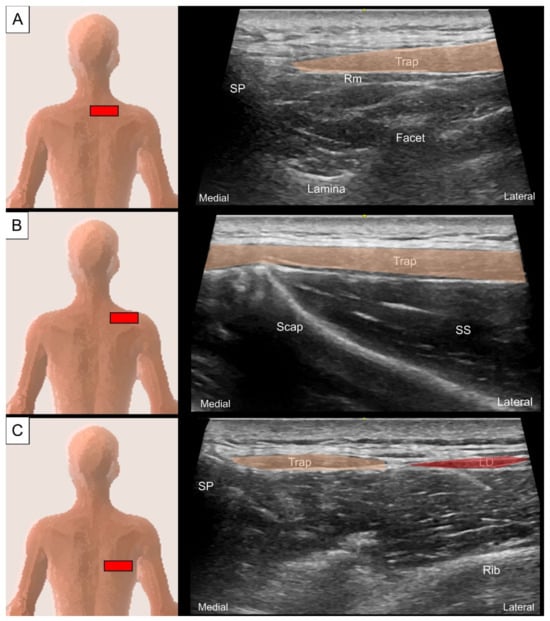

2.1.2. Sonographic Scanning

2.2.2. Sonographic Scanning

3.1.2. Sonographic Scanning